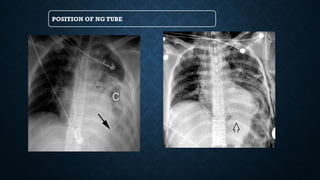

POSITION OF NG TUBE